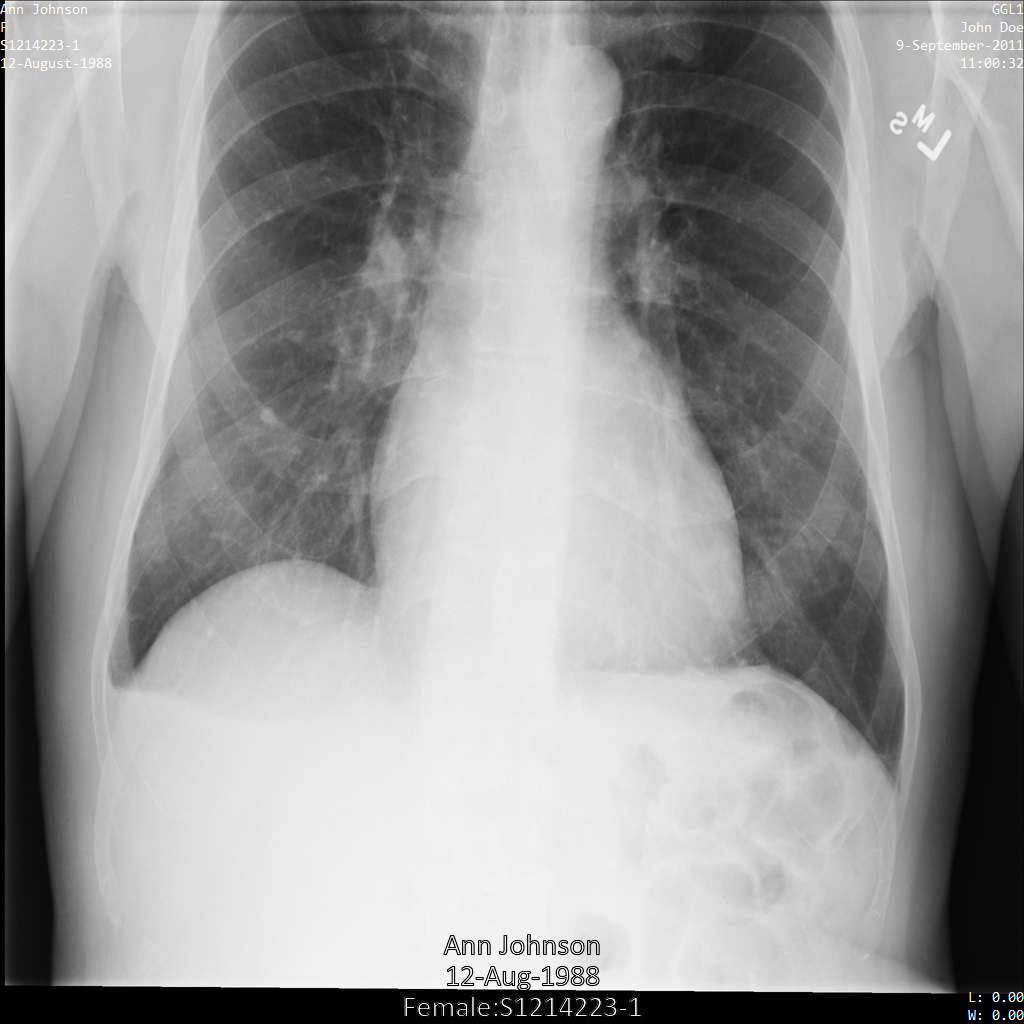

示例图片

本页面中的某些示例包含去标识化后的图片输出。每个示例都使用以下原始图片作为其输入。您可以将每个去标识化操作的输出图片与该原始图片进行比较,以查看该操作的效果:

使用 REDACT_ALL_TEXT

对图片进行去标识化处理后,图片如下所示。请注意,图片底部的所有已烧屏文字均已被遮盖。

REDACT_ALL_TEXT

对 DICOM 实例进行去标识化后的结果。使用“清理描述符”选项遮盖敏感文本

使用 REDACT_SENSITIVE_TEXT_CLEAN_DESCRIPTORS

对图片进行去标识化处理后,图片如下所示。请注意,图片底部并非所有已烧屏文字都被遮盖。文本 Female

仍会显示,因为 PatientSex (0010,0040)

不属于默认 DICOM infoType。

REDACT_SENSITIVE_TEXT_CLEAN_DESCRIPTORS

对 DICOM 实例进行去标识化后的结果。对 DICOM 标记进行去标识化